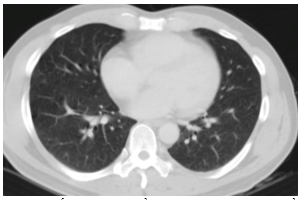

Chụp cắt lớp vi tính lồng ngực: Hình ảnh các nốt kính mờ rãnh liên thùy và màng phổi phải.Đám dải xẹp phổi thùy giữa phổi phải

Hình 7: Hình ảnh chụp cắt lớp vi tính lồng ngực sau điều trị, tổn thương u giảm kích thước sau 6 tháng điều trị (mũi tên vàng)

Chụp cắt lớp vi tính lồng ngực: Hình ảnh các nốt kính mờ rãnh liên thùy và màng phổi phải. Đám dải xẹp phổi thùy giữa phổi phải

Hình 8: Hình ảnh chụp cắt lớp vi tính lồng ngực sau 9 tháng điều trị

Đánh giá: Bệnh đáp ứng 1 phần

Điều trị tiếp: Alectinib 600mg/lần x 2 lần/ngày, uống trong bữa ăn